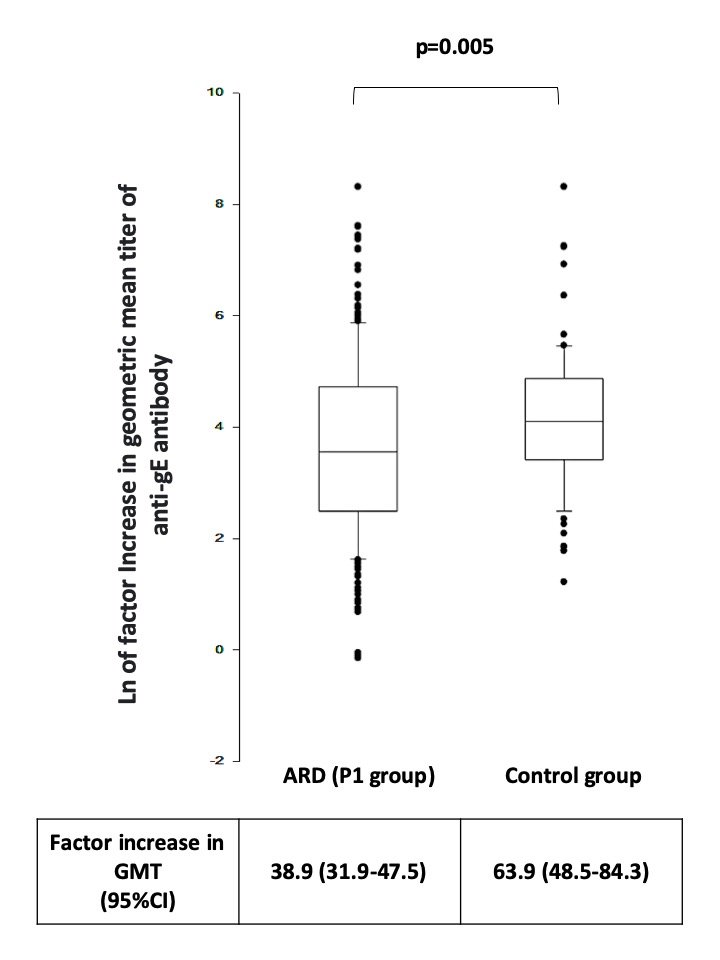

Interim analysis of a Phase 4 study of ARD (RA 25%, SLE 25%) patients shows recombinant herpes zoster vaccine(RZV) good safety profile, with no impact on disease activity (flare rates: 13.6% vs. 12.4%). Immunogenicity: 93% response in ARDs vs. 99% in controls. Rituximab & MMF… https://t.co/U3s48fLduX https://t.co/WTvD5shtXB

Antoni Chan MD (Prof) synovialjoints ( View Tweet)